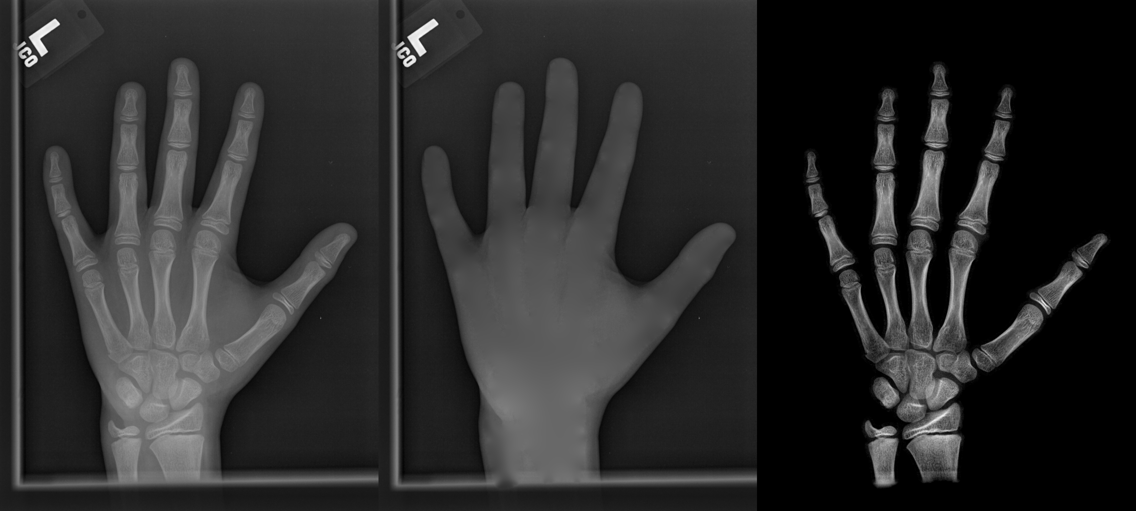

We performed three experiments for our method. First, we perform our method on several X-ray images, showing our method is not restricted by specific imaging objects. Second, we compared our method with image enhancement method and dehazing method, showing that our modification of the original dehazing indeed helps in this task. Third, we perform our method on a hand X-ray image dataset, showing its effectiveness and efficiency.

Several results from our method are shown in Fig. 7. The left column is the original input image. The right two columns are the soft tissue and bone image, respectively. It can be told that the soft tissue image is smooth as we assumed. Meanwhile, the bone image has better image contrast as desired. Moreover, our method can reach real-time performance on these X-ray images. The running time of our method on these images is reported in Table I.

In each panel of Fig. 10, the input image (left) is decomposed into soft tissue (middle) and bone image (right) by our method. Although we only show the first ten images from the data set, the results for the rest images are similar.

The bone images have better image contrast since the parameter is theoretically guaranteed. Such enhancement can also be directly told by radiologists. Such enhancement is good for bone diagnosis in practical applications.

Moreover, the running time of our method on such high resolution images is less than half second in the MATLAB language on a laptop. Therefore, it can achieve higher performance on a better hardware in real applications. If higher performance is required, our model can be solved by the parallel Laplace equation solver on a modern graphic process unit (GPU), which usually has thousands of cores.